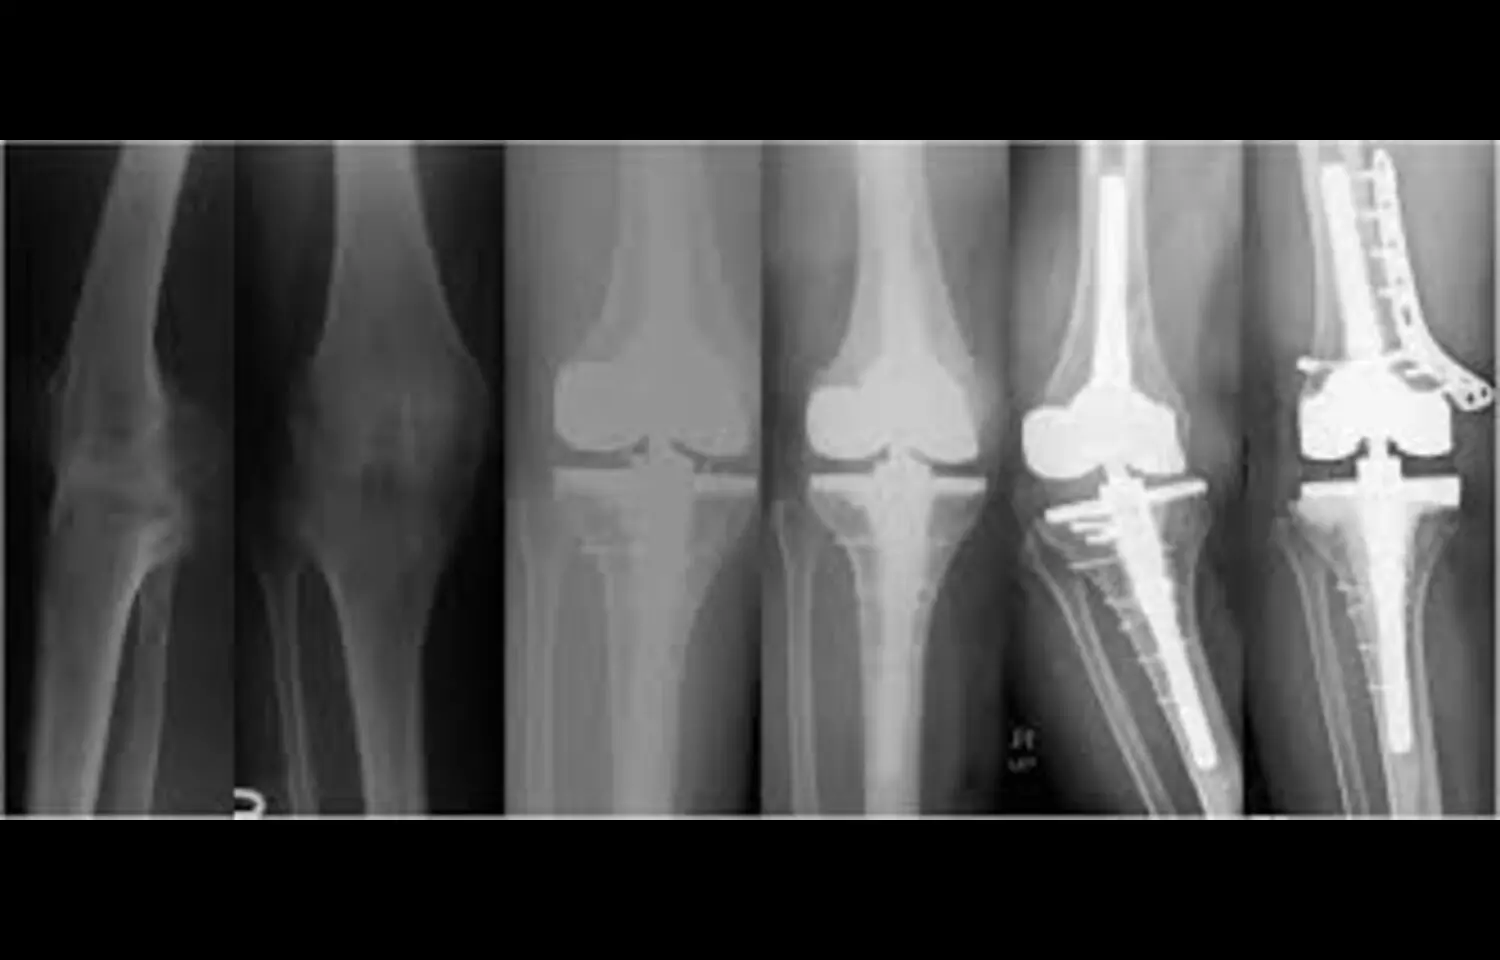

Total knee arthroplasty (TKA) is widely used to treat end-stage knee disorders, but its role in ankylosed knees has long been debated due to the technical complexity and heightened risk of complications. A recent study has provided important insights, showing that although patients with ankylosed knees experience lower recovery of range of motion (ROM) and face higher complication rates compared with conventional osteoarthritis cases, Total knee arthroplasty still delivers meaningful improvements in function, mobility, and quality of life. In this retrospective analysis, researchers evaluated outcomes of patients with ankylosed knees who underwent Total knee arthroplasty. Preoperatively, most patients had severely restricted or no motion, limiting independence and quality of life. After surgery, despite achieving less ROM than patients with non-ankylosed knees, participants reported significant improvements in flexion, extension, walking ability, and pain reduction. These functional gains translated into higher satisfaction levels and improved performance in daily living activities. However, the study also highlighted the elevated risk profile of Total knee arthroplasty in this population. Complications such as periprosthetic fractures, wound healing problems, prosthetic loosening, and infections occurred more frequently. Recovery of knee mobility was often incomplete, with gains falling short of those seen in routine arthroplasty. The findings emphasize the need for realistic preoperative counseling, careful surgical planning, and close postoperative monitoring. Despite these challenges, the clinical impact of Total knee arthroplasty in ankylosed knees was substantial. Even modest improvements in knee motion allowed patients to regain independence, reduce reliance on assistive devices, and improve psychosocial well-being. The study suggests that Total knee arthroplasty can be considered a viable and effective treatment option in patients with ankylosed knees, provided that both patients and surgeons are aware of the potential risks and limitations. Overall, this research reinforces the view that while Total knee arthroplasty in ankylosed knees carries higher complexity and complication rates, it remains a transformative intervention, improving mobility, functional independence, and quality of life in a patient group that otherwise faces profound disability.